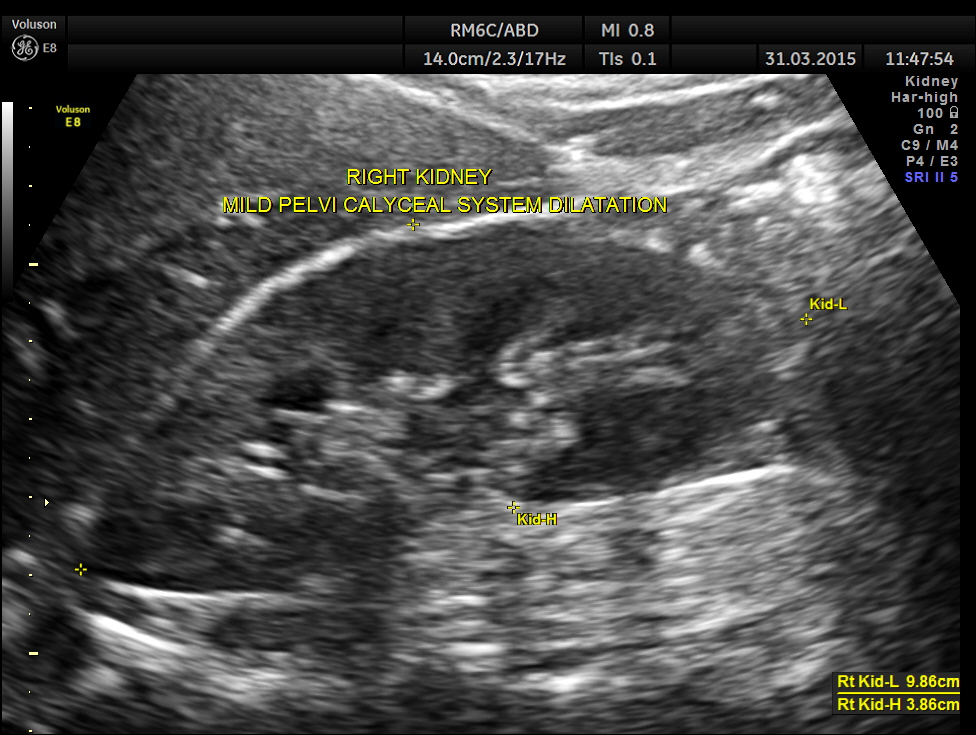

Ultrasound showed the following.

Right kidney shows mild pelvi calyceal dilatation.